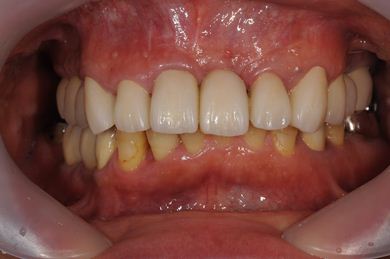

インプラントの症例写真 IMPLANT

骨再生インプラント治療

| 主訴 | 上前歯欠損部のインプラント治療を希望。 | ||||||||||||||||||||||||||||||||

| 治療方針 | 右上奥はソケットリフトにて上顎洞拳上してインプラント埋入を可能にし、上顎前歯部は骨再生法によりインプラント治療を行う。その他、補綴により口腔内全体の機能的審美的回復を行う。 | ||||||||||||||||||||||||||||||||

| 治療内容 | インプラント8本(GBR、ソケットリフト)、ハイブリッドセラミッククラウン17本(セラミック用土台5本) | ||||||||||||||||||||||||||||||||